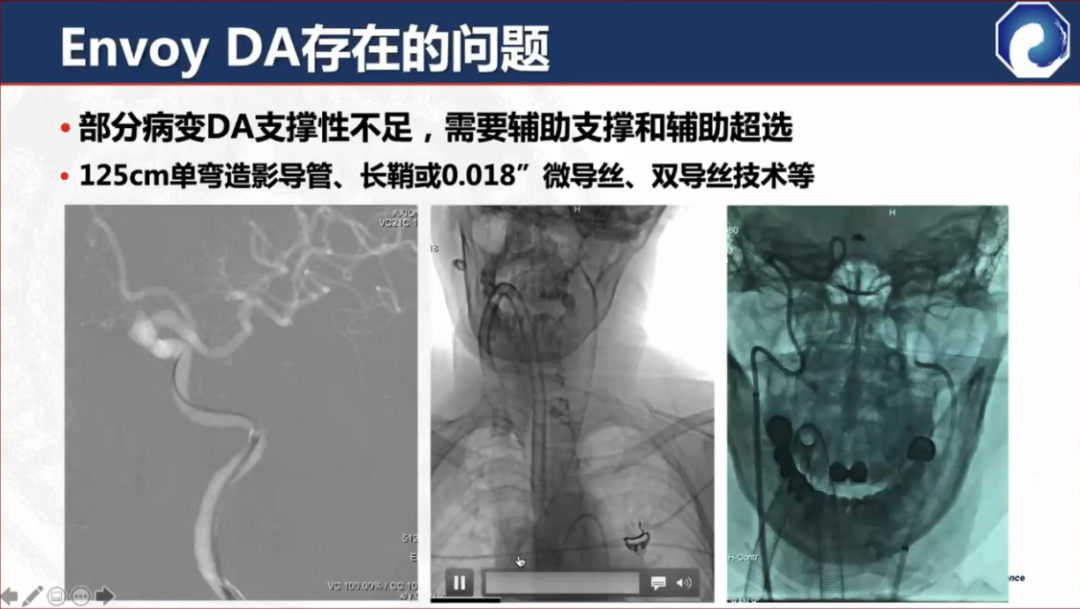

缺点:对于部分II型弓或比较迂曲的血管,弓部和近端支撑力不足

DA XB在DA的基础上做了改进,提升了支撑性